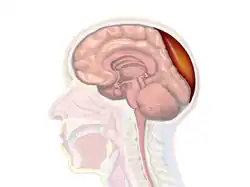

A diagram showing an epidural hematoma. A diagram showing an epidural hematoma.

Epidural hematoma is when bleeding occurs between the tough outer membrane covering the brain (dura mater) and the skull.[4] When this condition occurs in the spinal canal, it is known as a spinal epidural hematoma.[4]